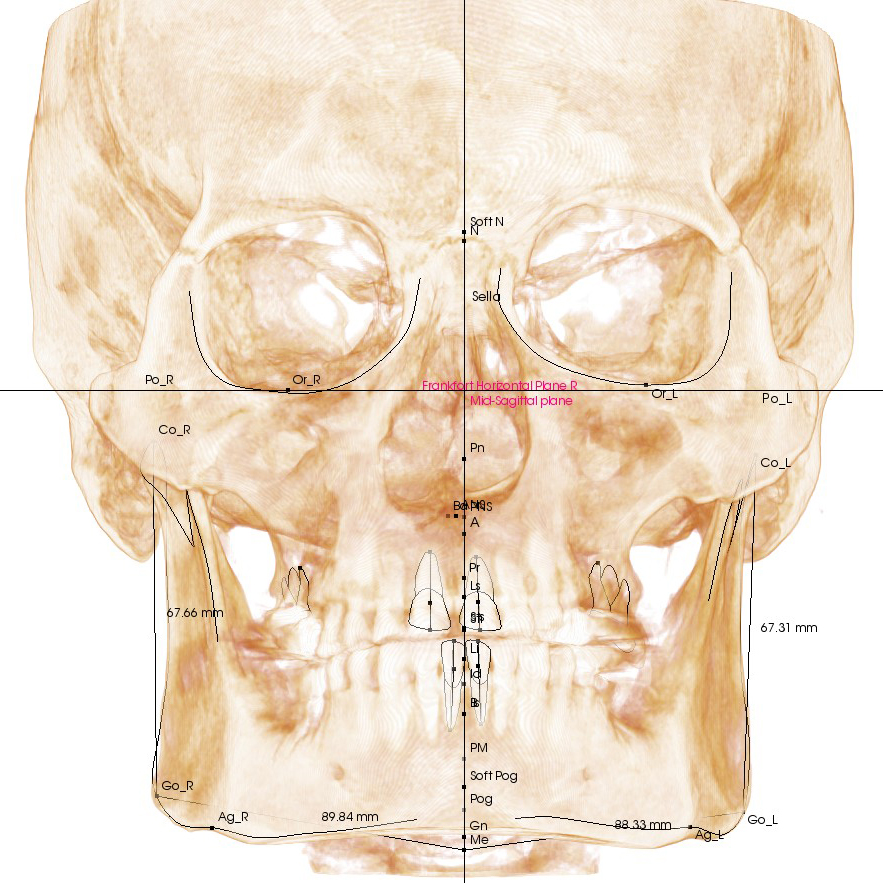

Современная диагностическая база

• Конусно-лучевая компьютерная томография